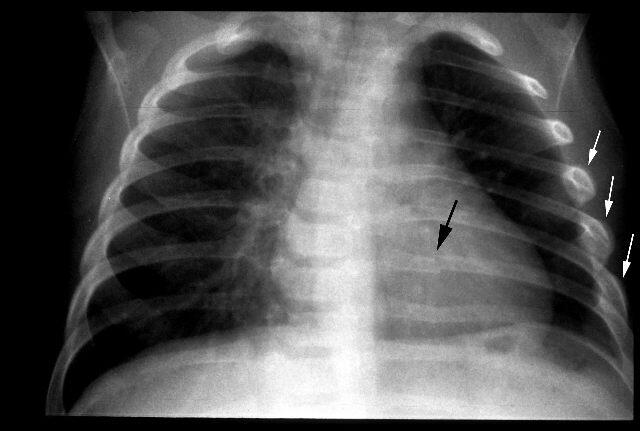

Медицина и диагностика: Аномалии ребер на рентгене